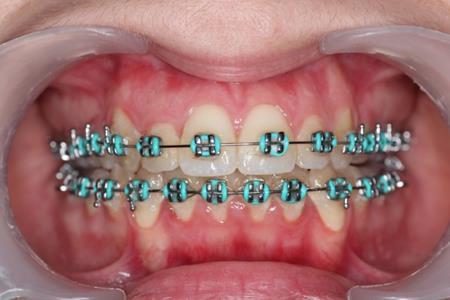

Figure 4.Intraoral photography at the start of the treatment.

After obtaining the informed consent the orthodontic treatment began and 0,22 Roth straight-wire fixed appliances were bonded. After leveling and aligning, during upper arch expansion, we took impressions and made intermediate study models. We noticed that palatal cusps of the upper premolars could not be intruded by classic mechanics. We decided to intrude first and second bicuspids to resolve the open bite. Skeletal anchorage was indicated and two orthodontic mini-implants were inserted on the palatal side between the premolars.